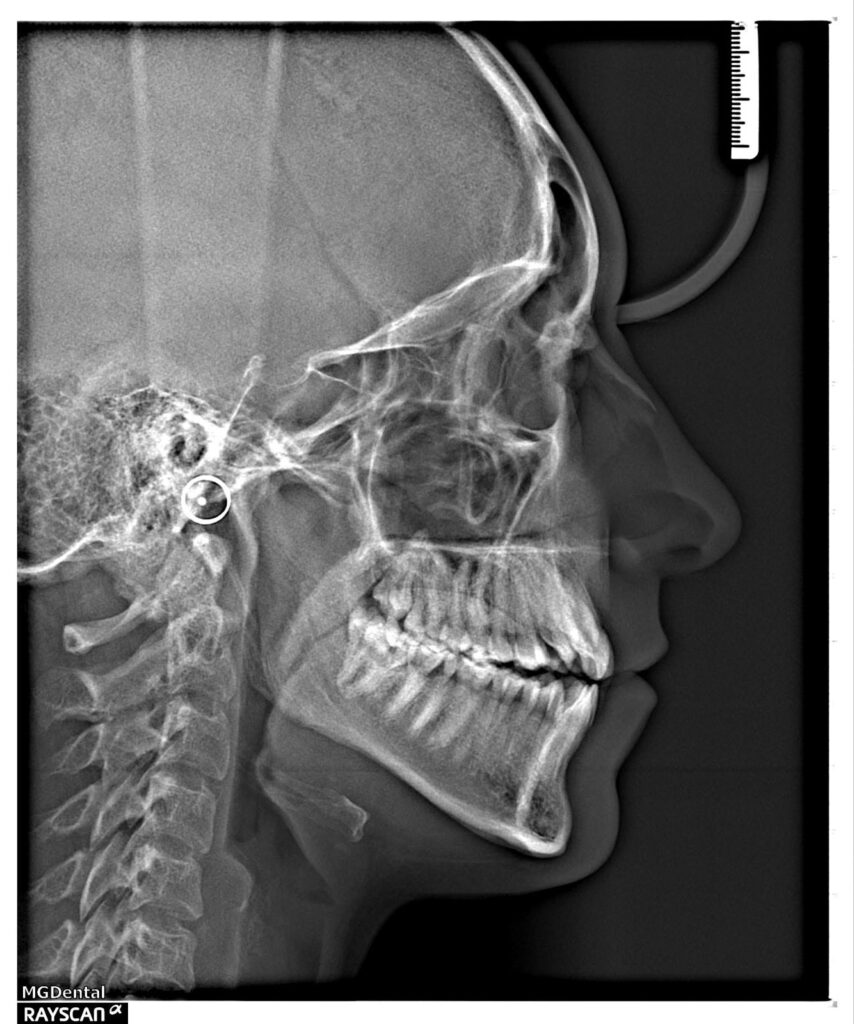

A 27-year-old female patient presented with class III malocclusion, 15 mm crowding in the upper arch, an anterior open bite, a lateral crossbite, and a total ABO score of 29. Her facial profile was straight with a retrusive maxilla, and the upper and lower incisors were retroclined. An extreme lack of midface support was also noted, and the constricted dental arches resulted in a poor smile width and dark buccal corridors. No myofunctional investigations were performed at the time, as they were initially considered unnecessary.

Adhering to the principles of Face First Orthodontics, the primary objective was to increase midface support by expanding the upper maxilla, fixing the cross bite, and aligning the teeth. Closing the open bite was a secondary objective.

Dr. Coca’s treatment plan followed the Biology First Orthodontics approach, which aims to minimize biological interventions. The treatment plan avoided extractions, stripping, TADs, corticotomy, and RPE. Given the facial requirements, a non-extraction treatment option was chosen.

The treatment began in 2017. Given the patient’s preference for less visible brackets, Damon Clear brackets were selected. High torque upper cuspids and low torque upper incisors were chosen to offer the best torque control for upper arch development. For the lower arch, there were no alternative bracket configurations available. Bite turbos were applied to the upper second molars.